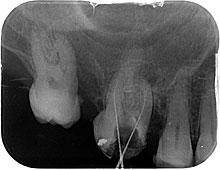

• Ein Röntgenbild wird erstellt, um die Anatomie der Wurzel und das eventuelle Vorliegen einer Entzündung im apikalen Bereich, d.h. um die Wurzelspitze herum, darzustellen. Siehe Röntgenbild: